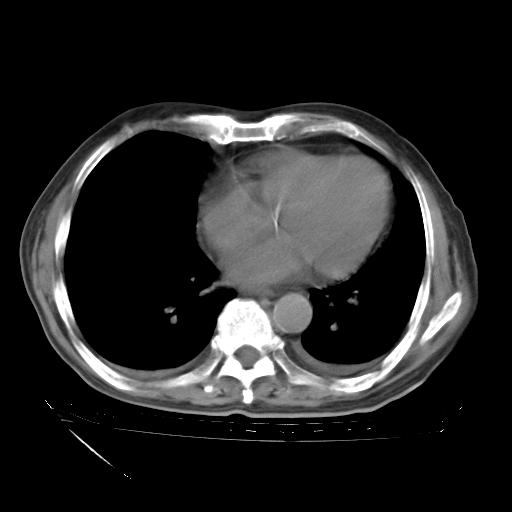

补充下:5月9日胸部CT:似乎已见双下肺胸腔积液了,鉴于目前有下肢水肿,肝功示:白蛋白低,应注意多浆膜腔积液(漏出液可能大?),需注意!

甲强龙80mg/日+抗结核治疗(异烟肼+利福霉素+乙胺丁醇)10天。复查肺部CT。

治疗10天肺部CT